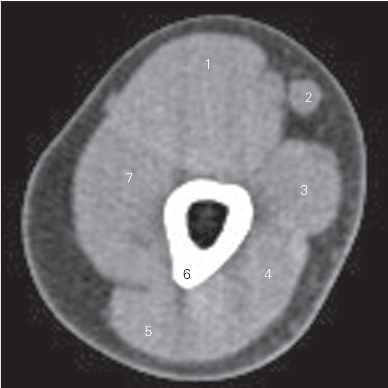

图4-25 经上臂中份的横断层CT图像(软组织窗)

1 肱二头肌 biceps brachii

2 贵要静脉 basilic vein

3 肱三头肌内侧头 medial head of triceps brachii

4 肱三头肌长头 long head of triceps brachii

5 肱三头肌外侧头 lateral head of triceps brachii

6 肱骨 humerus

7 肱肌 brachialis